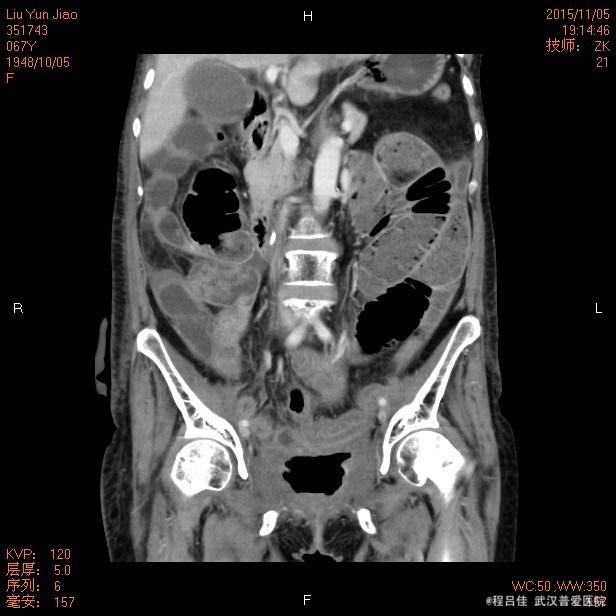

查体:腹部平坦,无胃肠型,无压痛及反跳痛,肠鸣音正常,阴道仍有粪渣样物质排出。 辅查: 膀胱镜检查:膀胱阴道瘘诊断明确 腹部CT:1.“宫颈癌行子宫全切术后+化疗后+回肠代膀胱造瘘术后+右肾造瘘术后"改变:回肠代膀胱;膀胱积气及膀胱壁增厚,膀胱后壁欠连续,并见后凸小囊腔,由于其后方阴道及直肠显示欠清楚,考虑膀胱阴道瘘可能性大,未能确定是否与直肠相通,请结合临床。 2、盆腔前腹壁下包裹性积液积气形成;腹壁切口区改变,盆腔术区肠管聚拢、结构紊乱,考虑粘连伴小肠低位不完全性机械性肠梗阻。 3.胆囊多发结石,肝S6囊肿,右肝内胆管轻度扩张。